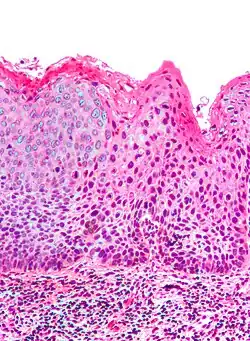

Micrograph of differentiated vulvar intraepithelial neoplasia. H&E stain.